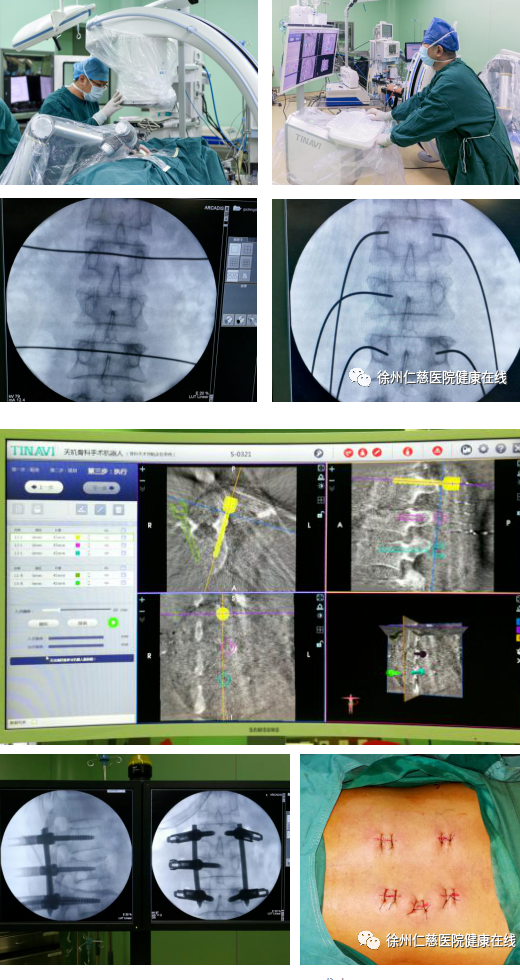

手术过程中,C型臂先扫描患者的三维图像,图像同步传输到骨科机器人系统。主刀医生通过导航系统辅助设计钉道,机械臂精确定位,不损伤其他脊椎关节,保证了神经安全和手术的有效性,所有操作一步到位。最后C型臂透视检查骨折复位,脊柱生理序列恢复满意,内固定物位置理想。术后当天患者的腰不疼了,过两天就下地锻炼走路了。

术中